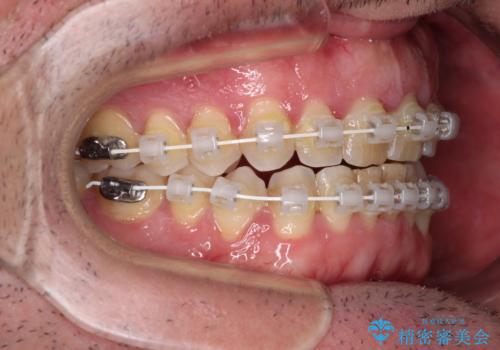

- 審美装置

前歯の非接触改善は、インビザラインの得意とするところですが、マウスピース矯正は絶対に継続できないとのことで、ワイヤー装置にて矯正治療を行うこととしました。

舌のトレーニング自体は簡単なものですが、無意識下でも舌が突出しないようにしなければならないため、毎日継続することが最大の難関です。

時間はかかりましたがトレーニングを頑張ってくださり、無事に前歯を接触させることができました。